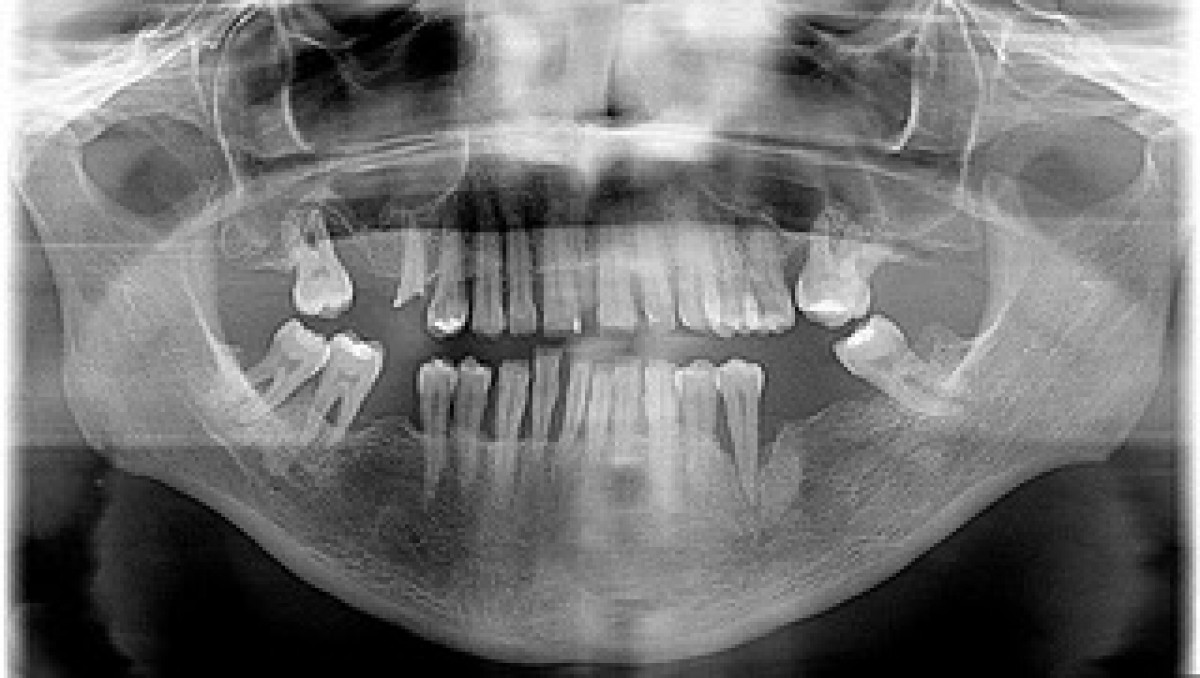

Statistacally significant higher values were registered for the RA group (P<0.05) for all periodontal indices except the number of teeth. The severity of periodontitis in all participants was slight or more than slight. The RA group showed also a significantly higher prevalence of moderate-to-severe periodontitis (64.2% vs. 34.9%, P<0.001).

The GI, BOP, and PPD showed positive relationships with several RA indices. The anti-Pg antibody titer had positive relationships with PPD, BOP, CAL, and periodontitis severity (table 1).